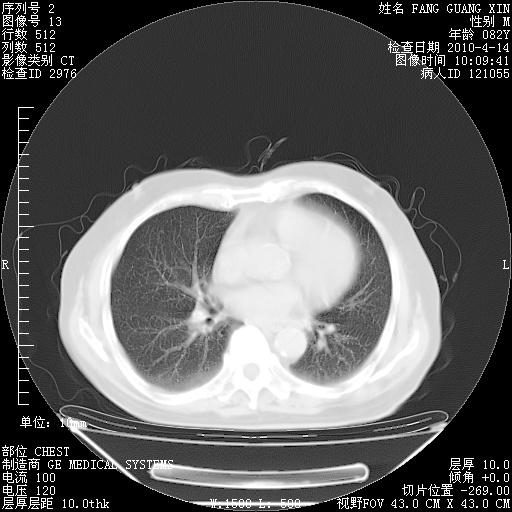

4月14日肺部CT

27.JPG

28.JPG

29.JPG

30.JPG

肺部CT平扫未见异常。